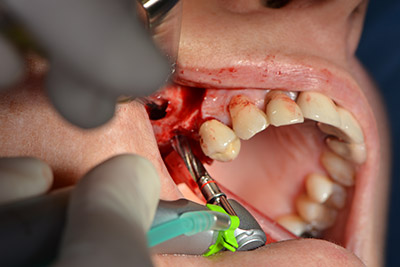

Следващата стъпка е синус лифт с непосредствено имплантиране. Implantmed е предварително настроен на първа позиция за букална фенестрация на стената на максиларния синус.

Фенестрацията е извършена при 35,000 rpm и след това носната лигавица е обработена по посока на челюстта (Фиг. 13 to 14).

Обработка на носната лигавица

Снимка 13

Наклонено пробиване с дрил

Снимка 14